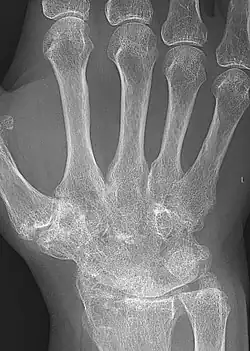

Ankylosis (from Greek ἀγκύλος (ankulos) 'bent, crooked') is a stiffness of a joint due to abnormal adhesion and rigidity of the bones of the joint, which may be the result of injury or disease. The rigidity may be complete or partial and may be due to inflammation of the tendinous or muscular structures outside the joint or of the tissues of the joint itself.[1]

When the structures outside the joint are affected, the term "false ankylosis" has been used in contradistinction to "true ankylosis", in which the disease is within the joint. When inflammation has caused the joint-ends of the bones to be fused together, the ankylosis is termed osseous or complete and is an instance of synostosis. Excision of a completely ankylotic shoulder or elbow may restore free mobility and usefulness to the limb. "Ankylosis" is also used as an anatomical term, bones being said to ankylose (or anchylose) when, from being originally distinct, they coalesce, or become so joined that no motion can take place between them.[1]